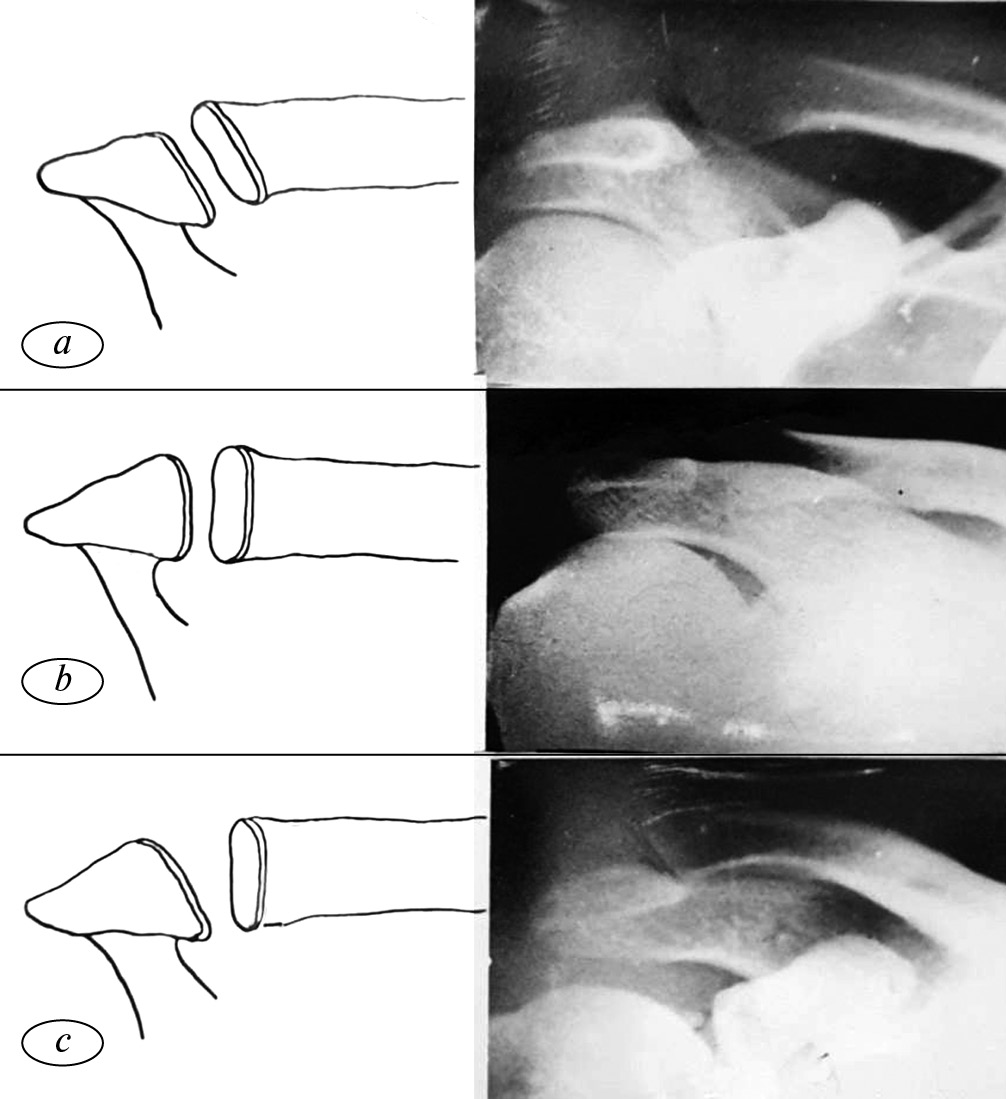

Мы проводили анатомические исследования на 50 нефиксированных и невскрытых трупах людей обоего пола в возрасте от 20 до 60 лет. Среди них мужчин было — 35, женщин — 15. При этом мы наблюдали три формы изменчивости расположения суставных поверхностей акромиона и ключицы: наклонную кнаружи (24 препарата из 50–48 %), вертикальную (16 препаратов — 32 %), смешанную (акромиально-наклонную кнаружи, ключично-вертикальную, 10 препаратов — 20 %) (рис. 1). Угол наклона суставных поверхностей акромиона и ключицы кнаружи всегда был острым (40–45 °С).

Рис. 1. Формы изменчивости расположения суставных поверхностей акромиона и ключицы: а — наклонная кнаружи; b — вертикальная; с — смешанная (акромиально-наклонная кнаружи, ключично-вертикальная)

Fig. 1. Forms of variability of the location of the articular surfaces of the acromion and clavicle: a — inclined outwards; b — vertical; c — mixed (acromially inclined outwardly, clavicularly vertical)